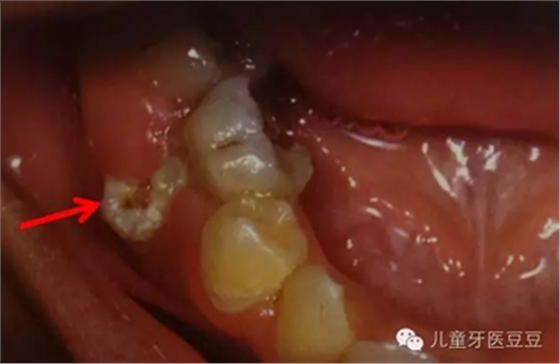

有時(shí)孩子的乳牙齲壞嚴(yán)重,已經(jīng)影響到了牙髓必須進(jìn)行根管治療(主要目的是通過治療,去除已經(jīng)壞死感染的牙髓組織,減少它們對牙齒根尖的不良影響,并使用可以吸收的材料將根管沖洗充填)。家長常常擔(dān)心乳牙要是沒有了牙髓,是不是恒牙就不能正常替換;是不是恒牙也就沒有了牙髓。這些都是誤解,乳牙和恒牙有自己獨(dú)立的牙髓系統(tǒng),即使乳牙沒有牙髓恒牙也可以替換。相反如果乳牙反復(fù)感染(這是往往牙髓早已壞死也是沒有正常的牙髓的),導(dǎo)致根尖周炎則會影響恒牙的發(fā)育和萌出。

乳牙反復(fù)根尖發(fā)炎導(dǎo)致繼承恒牙發(fā)育不良